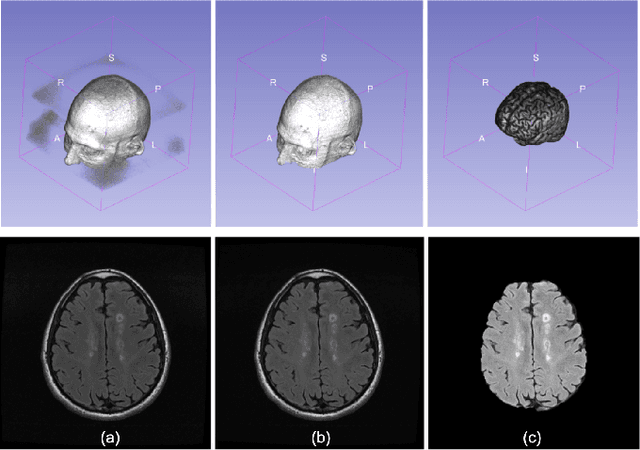

Abstract:Multiple sclerosis (MS) is a chronic inflammatory and degenerative disease of the central nervous system, characterized by the appearance of focal lesions in the white and gray matter that topographically correlate with an individual patient's neurological symptoms and signs. Magnetic resonance imaging (MRI) provides detailed in-vivo structural information, permitting the quantification and categorization of MS lesions that critically inform disease management. Traditionally, MS lesions have been manually annotated on 2D MRI slices, a process that is inefficient and prone to inter-/intra-observer errors. Recently, automated statistical imaging analysis techniques have been proposed to extract and segment MS lesions based on MRI voxel intensity. However, their effectiveness is limited by the heterogeneity of both MRI data acquisition techniques and the appearance of MS lesions. By learning complex lesion representations directly from images, deep learning techniques have achieved remarkable breakthroughs in the MS lesion segmentation task. Here, we provide a comprehensive review of state-of-the-art automatic statistical and deep-learning MS segmentation methods and discuss current and future clinical applications. Further, we review technical strategies, such as domain adaptation, to enhance MS lesion segmentation in real-world clinical settings.